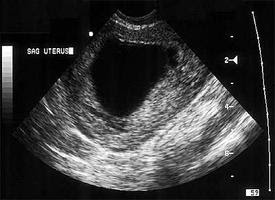

Mengetahui Tanda-Tanda Kehamilan Kosong - Bidanku.com

Mengetahui Tanda-Tanda Kehamilan Kosong - Bidanku.com